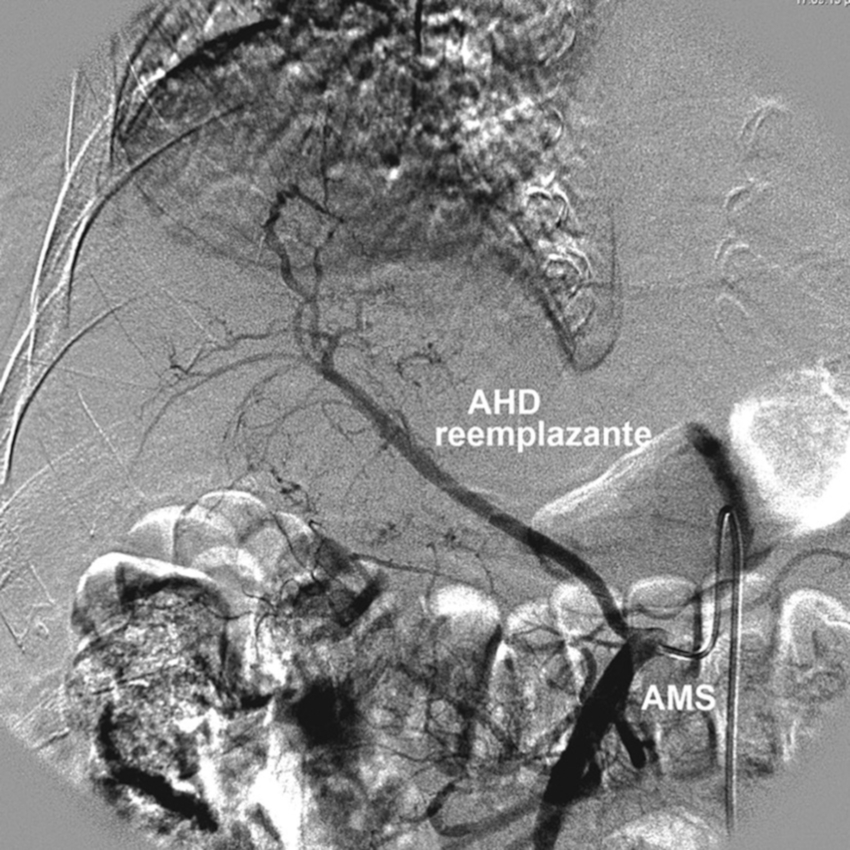

Tipo 3: AHD aberrante con origen en la AMS. AHI con origen en la AHC (Figs. 6 y 7).

Tipo 6: AHD y AHI con origen en la AHC. AHD accesoria desde la AMS (Figs. 11 y 12).

Tipo 9: la AHC emerge de la AMS (Fig. 17).